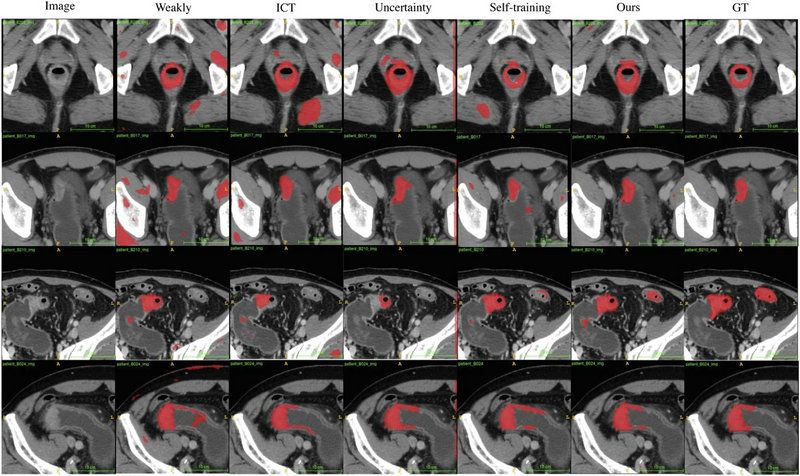

团队利用来自best365中国官方网站附属第六医院和喀地一院的923例有标注结肠癌CT影像和2670例无标注结肠癌CT影像作为SOUSA框架的训练数据集,并利用417例结肠癌CT影像对SOUSA框架进行验证,结果显示其自动分割效果优于现有的弱监督和半监督学习模型。与目前最先进的方法ICT (Verma et al.,2019)、不确定性感知(Yu et al.,2019)和自我训练相比,SOUSA框架在每个数据比率上都达到了最佳性能。此外,当数据集的大小有限时,SOUSA框架的性能甚至与使用密集注释的模型的性能相当。

对肠癌数据集使用不同方法的自动分割结果